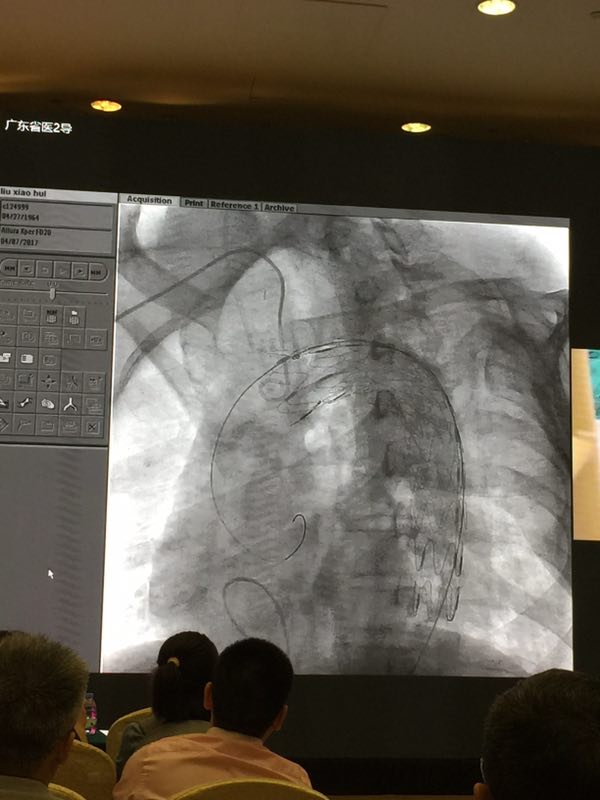

CT测量显示患者近端瘤颈直径为30.93mm,具有丰富临床经验的刘媛教授选用了彩神在线网信彩票-彩神通免费版下载-彩神8争霸vlll-彩神购彩购彩大厅-彩神软件陆立根免费版-彩神ll争霸3-彩神ll彩神8-彩神ll争霸彩票-拼搏在线彩神网网页版科技公司34200的 Ankura™胸主动脉覆膜支架对患者胸主动脉夹层进行修复。Ankura™胸主动脉覆膜支架的锥形设计使支架主体能够更好地顺应真腔形态,减少对远端内膜的损伤及相关并发症的发生,对于假腔大、真腔受压明显的主动脉夹层患者尤为适用;且支架多锥度,多长度,可根据病人情况配合临床制定个性化手术方案。刘教授行云流水般的娴熟技巧配合Ankura™胸主动脉覆膜支架支撑性好,定位准确的特点,使得整台手术进行得非常顺利。术后造影显示,支架植入后形态佳,定位准确,支架内血流畅通,无内漏。这几近完美的结果,让全场爆发出热烈的掌声。黄连军教授和冯睿教授也在直播现场对彩神在线网信彩票-彩神通免费版下载-彩神8争霸vlll-彩神购彩购彩大厅-彩神软件陆立根免费版-彩神ll争霸3-彩神ll彩神8-彩神ll争霸彩票-拼搏在线彩神网网页版科技Ankura™胸主动脉覆膜支架系统给予了高度评价。

图:Ankura™胸主动脉覆膜支架植入后形态佳、无内漏